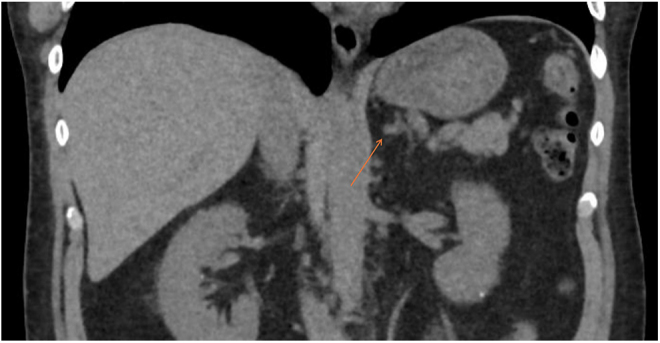

Summary: We describe a case of a 42-year-old gentleman, 5 years post-transsphenoidal surgery (TSS) for pituitary-dependent Cushing's disease, initially presenting with malignant hypertension. Despite an initial improvement in his blood pressure post-TSS, he was found to be persistently hypertensive on follow-up despite no clinical or biochemical evidence of recurrence of hypercortisolism. His blood pressure remained elevated despite five antihypertensive agents. His renin concentration was <5 mIU/L (9-103.5) and aldosterone concentration was 877 pmol/L (0-670). A subsequent CT of the adrenals showed a 1.2 cm left adrenal nodule. He was not suitable for adrenal vein sampling (AVS) at this time due to difficult-to-control hypertension. Biochemistry was difficult to interpret in the context of a multitude of interfering medications, which were necessary given his difficult-to-control hypertension and hypokalaemia. Once suitable, his initial AVS was unsuccessful due to failure to cannulate the right adrenal vein. He was given the further options of repeat AVS vs 11C-metomidate PET vs medical management of his blood pressure. He proceeded with a repeat AVS, with successful cannulation of both adrenal veins. This showed evidence of hyperaldosteronism on the left side, with a lateralisation index of 39.5 and a contralateral suppression index of 0.28. He proceeded with a robotic left adrenalectomy, leading to significant improvement in his blood pressure, dropping from a mean reading of 142/85 during daytime and 150/88 mmHg at nighttime on five antihypertensive agents to normotensive levels of 114/77 mmHg on two agents.